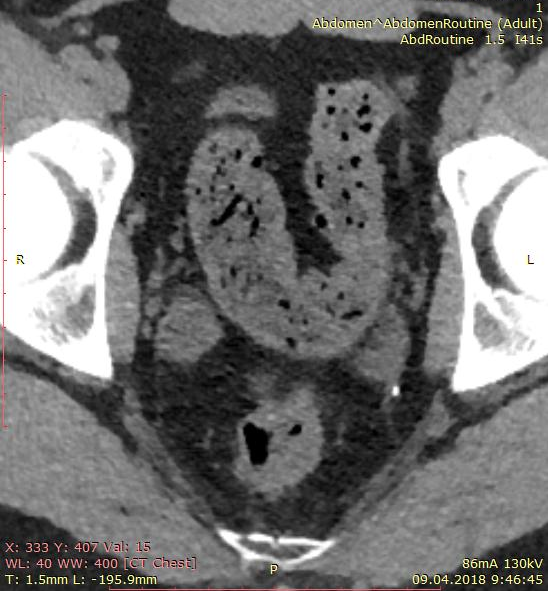

КТ диагностика тубоовариального абсцесса: Подходы и изображения

Раздел: Объективный взгляд